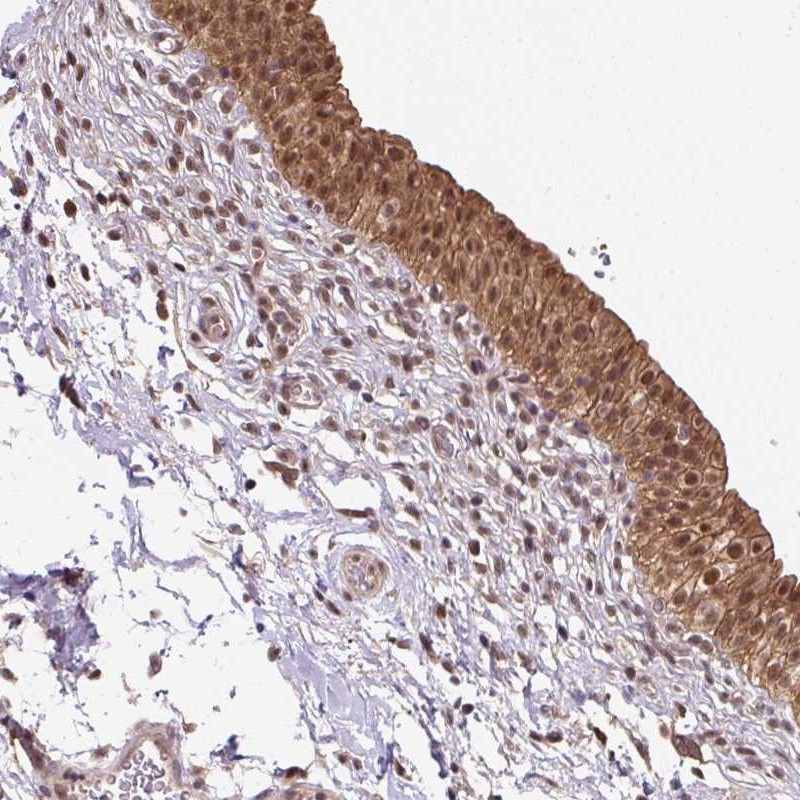

Immunohistochemical staining of human urinary bladder shows moderate nuclear, cytoplasmic and membranous positivity in urothelial cells.